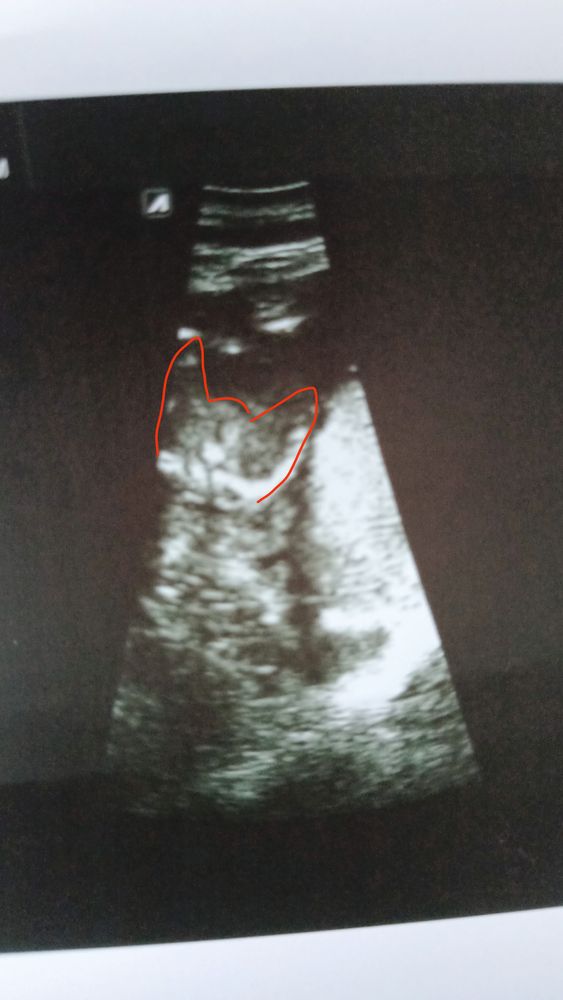

Неделю назад ходила на второй скрининг срок был ровно 16+0. Минут 20 не могли поймать нужный ракурс и в конце концов сказали что скорее всего %80 процентов девочка. Дали вот такой снимок. Как вы думаете могли ошибиться?

Неделю назад ходила на второй скрининг срок был ровно 16+0. Минут 20 не могли поймать нужный ракурс и в конце концов сказали что скорее всего %80 процентов девочка. Дали вот такой снимок. Как вы думаете могли ошибиться?

Не понятно ничего, ножки скрещены и поджаты, подрастет станет лучше видно 😉

Качество снимка не очень хорошее, но вроде девочка.

Красным цветом вообще голова кошачья нарисована 😅😅